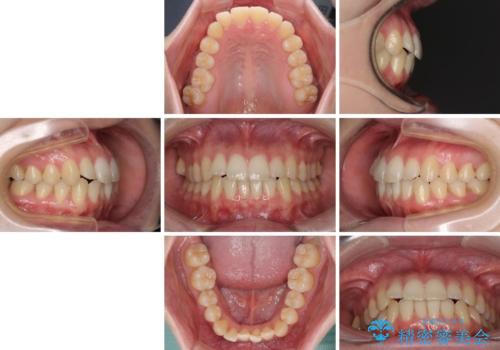

- ちょっとしたデコボコを整えたいとのことで来院された患者様です。

歯列不正は軽微であったため、インビザライン・ライトにより、費用を抑えて矯正治療を行うこととしました。

上下前歯の捻れが改善され、患者様には大変満足していただきました。